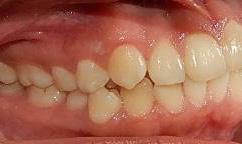

Paciente de 16 años 3 meses diagnosticada con clase II esquelética, clase II molar bilateral, clase II canina bilateral, apiñamiento superior severo e inferior moderado, el canino 23 ectópico, la línea media superior desviada 1 mm izquierda, línea media inferior 2 mm derecha.

Estudios de inicio extraorales fotografía de frente sonrisa (Figura 1) el perfil convexo.

Estudios de inicio intraorales en la fotografía de frente, tenemos la línea media dental superior se encuentra desviada a 1 mm a la izquierda y la línea media dental inferior se encuentra desviada 2 mm a la derecha (Figura 2). En la oclusal superior la forma de arco cuadrada (Figura 3). En la lateral derecha una relación molar clase II y relación canina clase II (Figura 4), izquierda una relación

Dentista y Paciente 42 Caso clínico

Figura 1. Extraoral frente sonrisa y perfil de inicio. Figura 2. Intraoral de frente.

molar clase II y relación canina clase II.